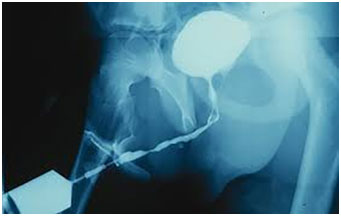

Retrograde urethrogram (RGU) is another radiology test to evaluate urethral strictures. This test basically entails placing a small urinary catheter in the last part of the urethra (closest to the tip of the penis). Approximately 10 cc of an iodine contrast material is slowly injected in the urethra via the catheter. Then, radiographic pictures are taken under fluoroscopy to assess any obstruction or impairment to the flow of the contrast material that can suggest urethral stricture. This test provides useful information about the location, extent, and size of any narrowing in the urethra as well as the shape of any possible abnormalities.

Anterograde cystourethrogram is a similar test but can only be done if there is a suprapubic catheter in place (a urinary catheter placed in the bladder through the skin in the lower abdomen). Iodine contrast is then injected into the bladder via the catheter and its flow out of the urethra is radiographed under fluoroscopy.

युरिन नली के अन्दर दवा डालते हुए (RGU) एवं मुत्र निकासी के समय (MCU) एक्स रे करना।